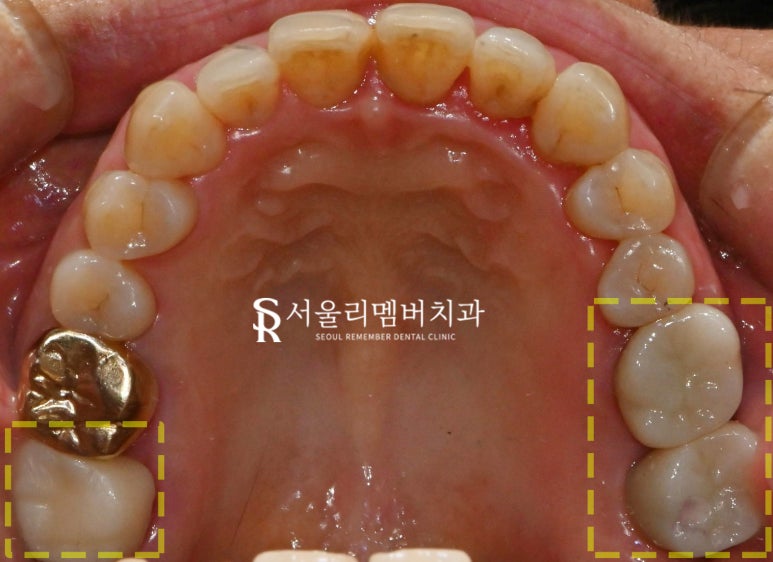

내원 당시 사진과 개선 후의 사진을

비교하면 큰 변화를 확인할 수 있습니다.